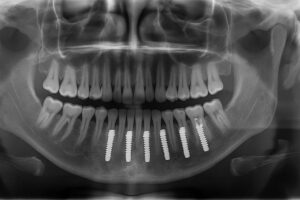

All-on-4® / full-arch solutions

All-on-4® and other full-arch options replace a full upper or lower set of teeth using four to six implants. They can often be done with fewer surgeries and provide immediate function with temporary teeth, making them a fast way to regain a full smile.